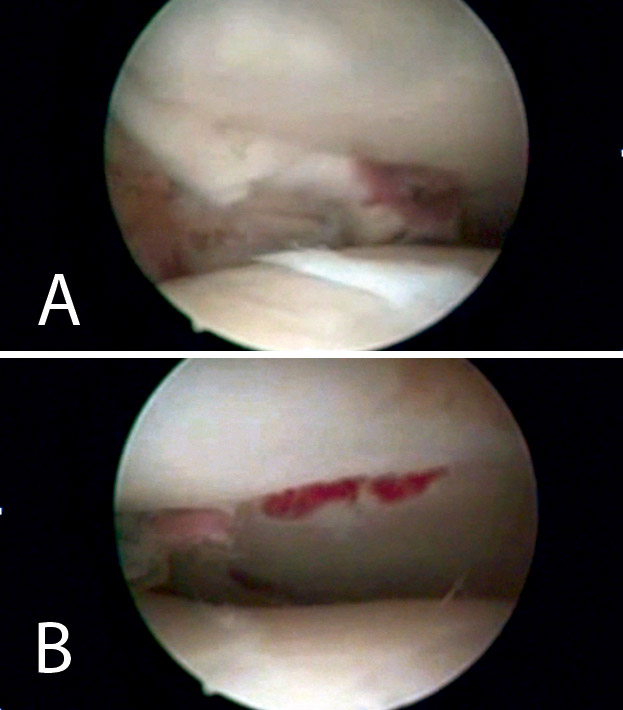

Figura 8. Percusión del fragmento con el impactor, control radioscópico de la posición del impactor e imagen artroscópica del escalón articular antes de la reducción.

Figura 9. Imagen artroscópica de la reducción del fragmento hundido y del trazo articular.

Figura 10. Colocación de los tornillos. Control radioscópico.

Figura 11. Control radiológico anteroposterior y lateral.